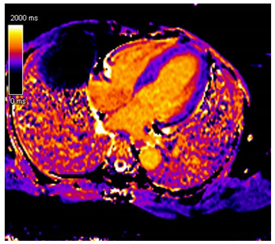

| CMR Parameter | Key CMR Findings | Illustrative Example |

|---|---|---|

| Cardiac Structure and Function |

| ![]() |

| T1 time | Elevated native T1 time | ![]() |

| T2 Time | Possibly elevated T2 time but not as high as reported in myocarditis or myocardial infarction | ![]() |

| LGE | Diffuse patchy LGE of the left ventricle LGE of the atria and the right ventricle may be present | ![]() |

| ECV | Markedly elevated ECV | ![]() |